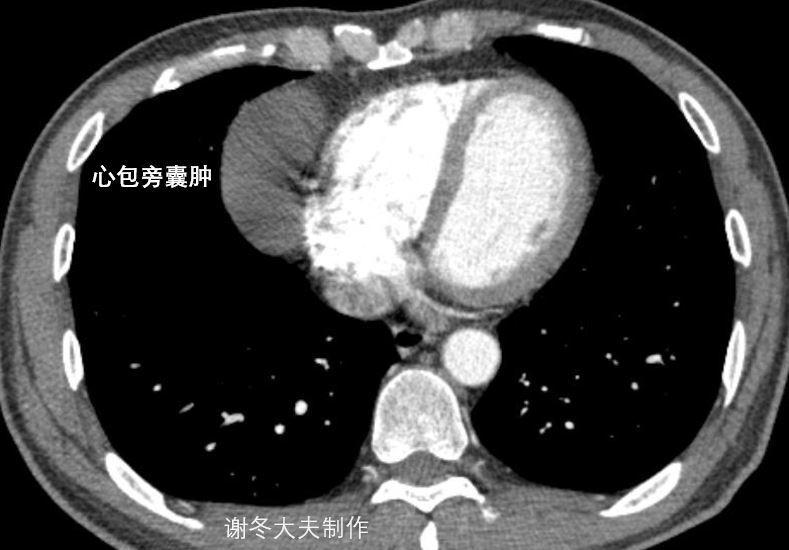

【每日一例 | 432期】19张图带你认识异位胸腺瘤